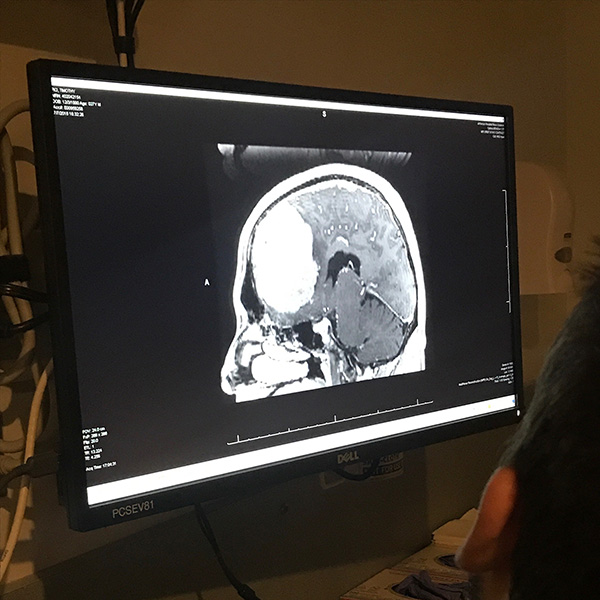

An MRI scan on a computer monitor shows a grapefruit-sized meningioma tumor.

That led to a CT scan and an MRI. As soon as those came back, they told me I wasn’t leaving. They said, “We need to do surgery as soon as we can.” That’s when they found a large tumor the size of a grapefruit or a softball.